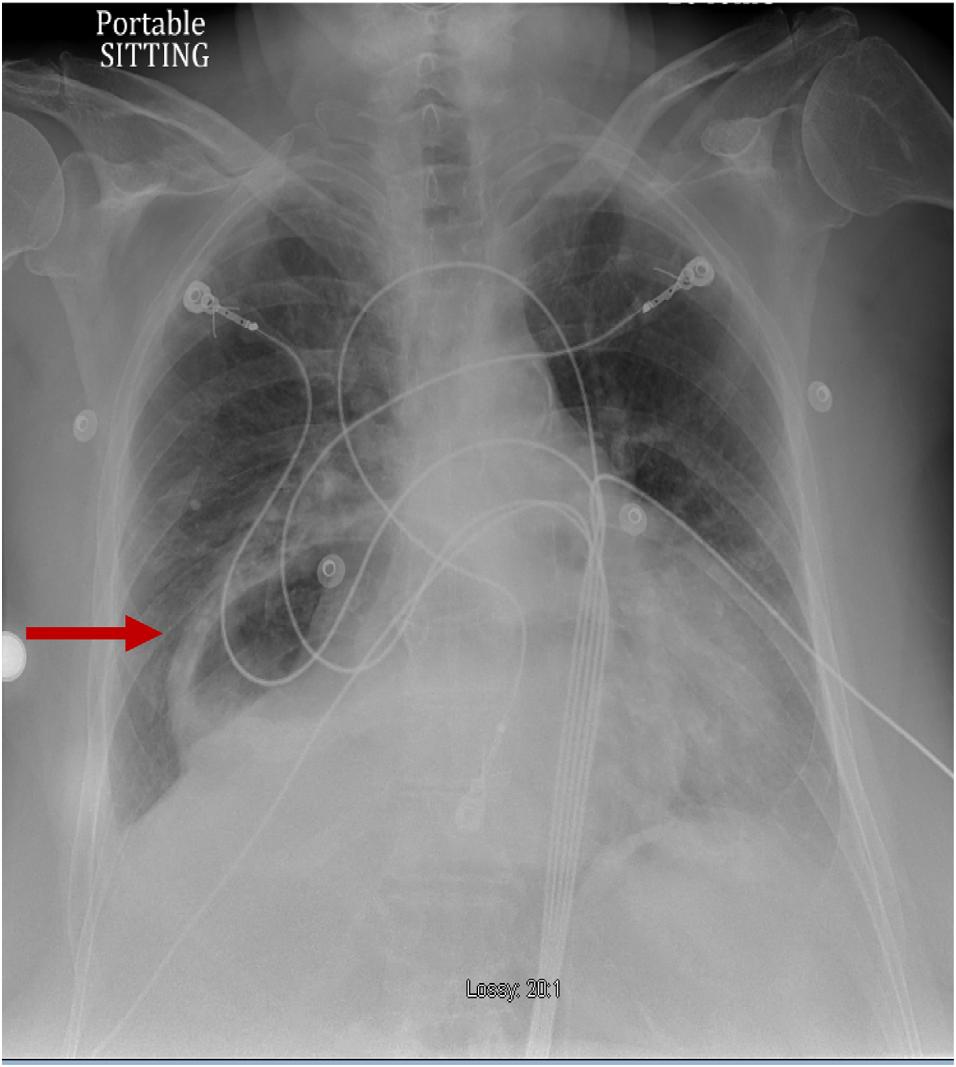

Achestradiograph(CXR)(Image1)showedalargehiatal herniawithtracebilateralpleuraleffusionsanddisplacement ofthegastricbubbletotheright.Computedtomography (CT)withcontrastofthechest/abdomen/pelvis(Images2 and 3)demonstratedalargehiatalherniawithmostofthe stomachinthechest,associatedvolvulus,bilateralpleural effusions,rightgreaterthanleft,andacomplex,partially fluid-filledcollectionalongtheposterioraspectofthehiatal

Anterior-posteriorchestradiographdemonstratinglarge hiatalherniawithdisplacementofthegastricbubble(arrow)from lefttoright.

Image3. Transverseviewofcomputedtomographyofthechest/ abdomen/pelviswithanarrowindicatingpartially fluid-filled collectionposteriortoalargehiatalherniasuspiciousfor esophagealperforation.

Image1. Image2. Coronalviewofcomputedtomographyofthechest/ abdomen/pelvisshowinglargehiatalhernia(arrow).Thepatientunderwentanexploratorylaparotomy,which confirmedthepresenceofanesophagealrupturenearthe squamocolumnarjunctionandrevealedthepresenceofa gianthiatalherniawithanassociatedupside-downstomach. Surgicalrepairoftheesophagealperforationandgastropexy wasperformed.Thepatientwasadmittedtothesurgical intensivecareunitforatotalof fivedaysduringwhich shehadanepisodeofatrial fibrillationwithrapidventricular responsethatresolvedaftermetoprololanddiltiazem.